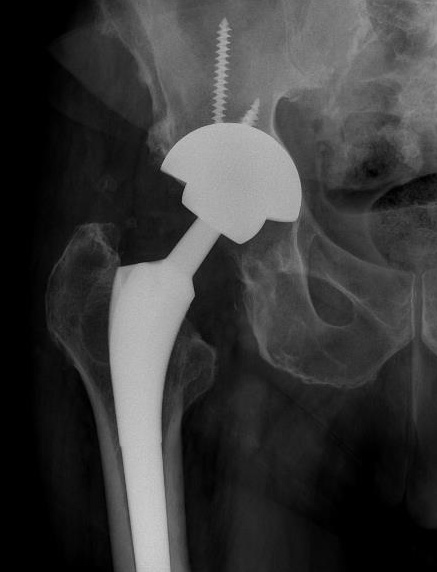

Results of revision

Crawford et al J Arthroplasty 2019

- revision of 2023 metal on metal THA

- failure average 5 years post primary surgery

- acetabulum revised in 92% of cases

- reoperation in 14%

- re-revision in 8%